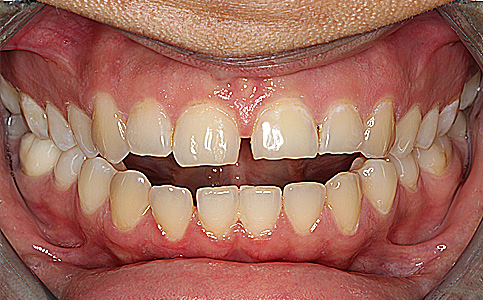

Pacjent zgłosił się do naszej kliniki ponieważ marzył o pięknym uśmiechu. Jego metamorfoza była wielospecjalistyczna. Pierwszym etapem było leczenie biologiczne, następnie uzupełnienie braków zębowych implantami oraz wykonanie koron pełnoceramicznych na zęby górne. Dzięki temu Pacjent odzyskał pewność siebie i zdrowy uśmiech.